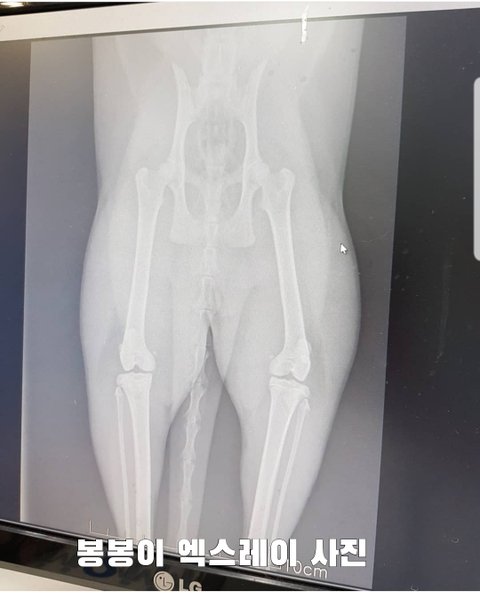

울세째 봉봉이는 확찐냥이 아니고 다만 털빨이다 털때문이다 우겨봤지만...

빼박 증거에 ㅋㅋㅋㅋㅋㅋㅋ

봉봉이가 다리를 조금 저는거 같아서 엑스레이를 찍었더니 엑스레이 보자마자 수의사님도 훗ㅋㅋㅋ 저도 순간 헉!! ㅋㅋㅋㅋㅋ

오늘부터 츄르 금지!!!